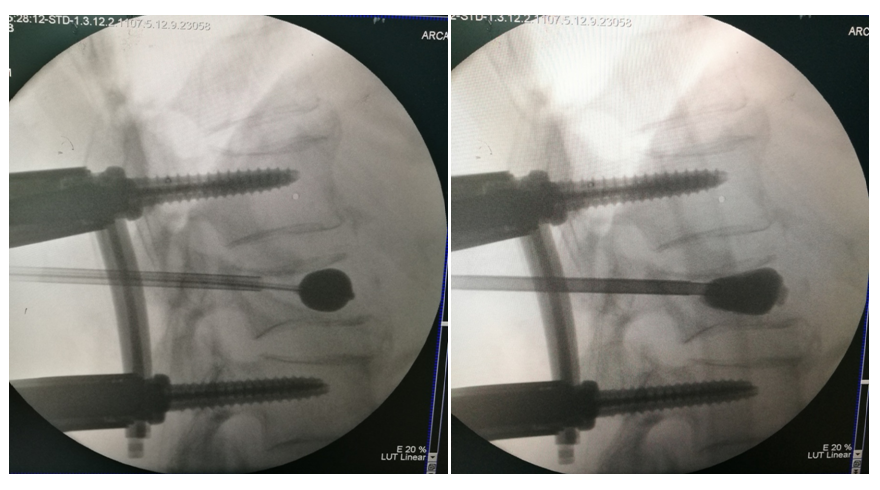

手术治疗

术后影像学

手术治疗:T10-T12棘突椎板切除;T11 截骨后凸矫形;T9-L1椎弓根固定,均为骨水泥螺钉,安放横联两根;T10/11及各椎板后方大量植异体骨及自体骨。

术中透视